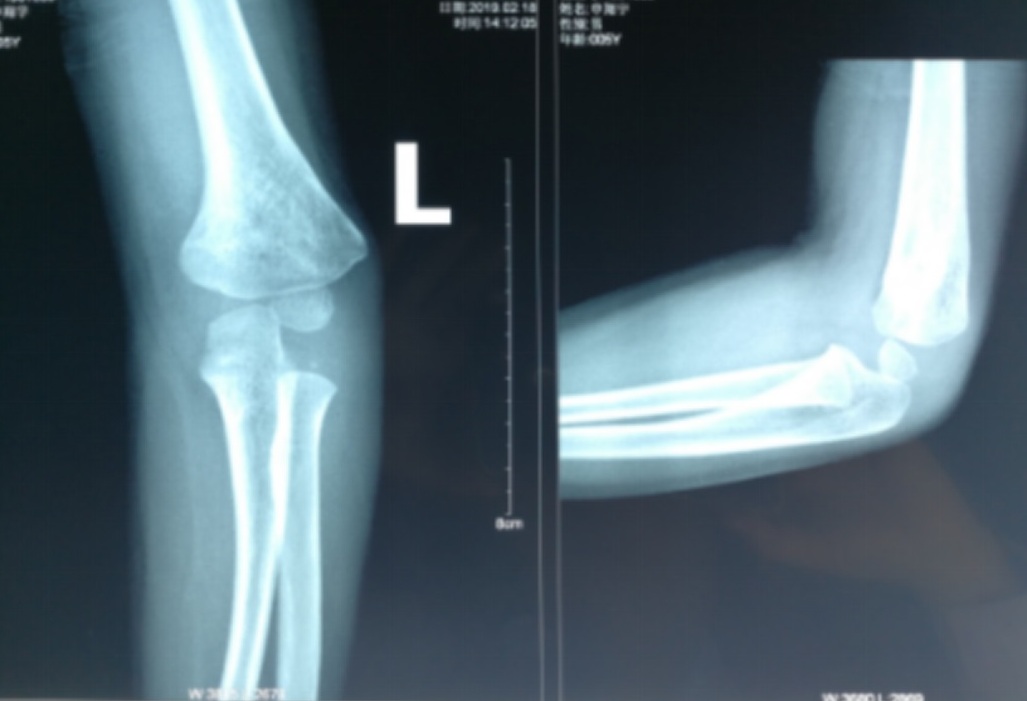

小明是一个7岁的小男孩,不慎摔伤胳膊肘。经过X线检查后,结果提示小明肱骨髁上骨折。医生建议做微创手术治疗,小明妈妈心疼孩子,选择了石膏固定保守治疗,医生给小明施行手法复位后石膏外固定,再做X线复查后示骨折复位良好。医生对小明父母说,有一点需要提醒的是,别看现在复位效果好,但容易出现一种并发症,就是胳膊往里拐~~医学专业术语就是:肘内翻。后来小明拆了石膏后发现胳膊向内拐了,出现原因是之前骨折的地方没有长好,发生了畸形愈合。